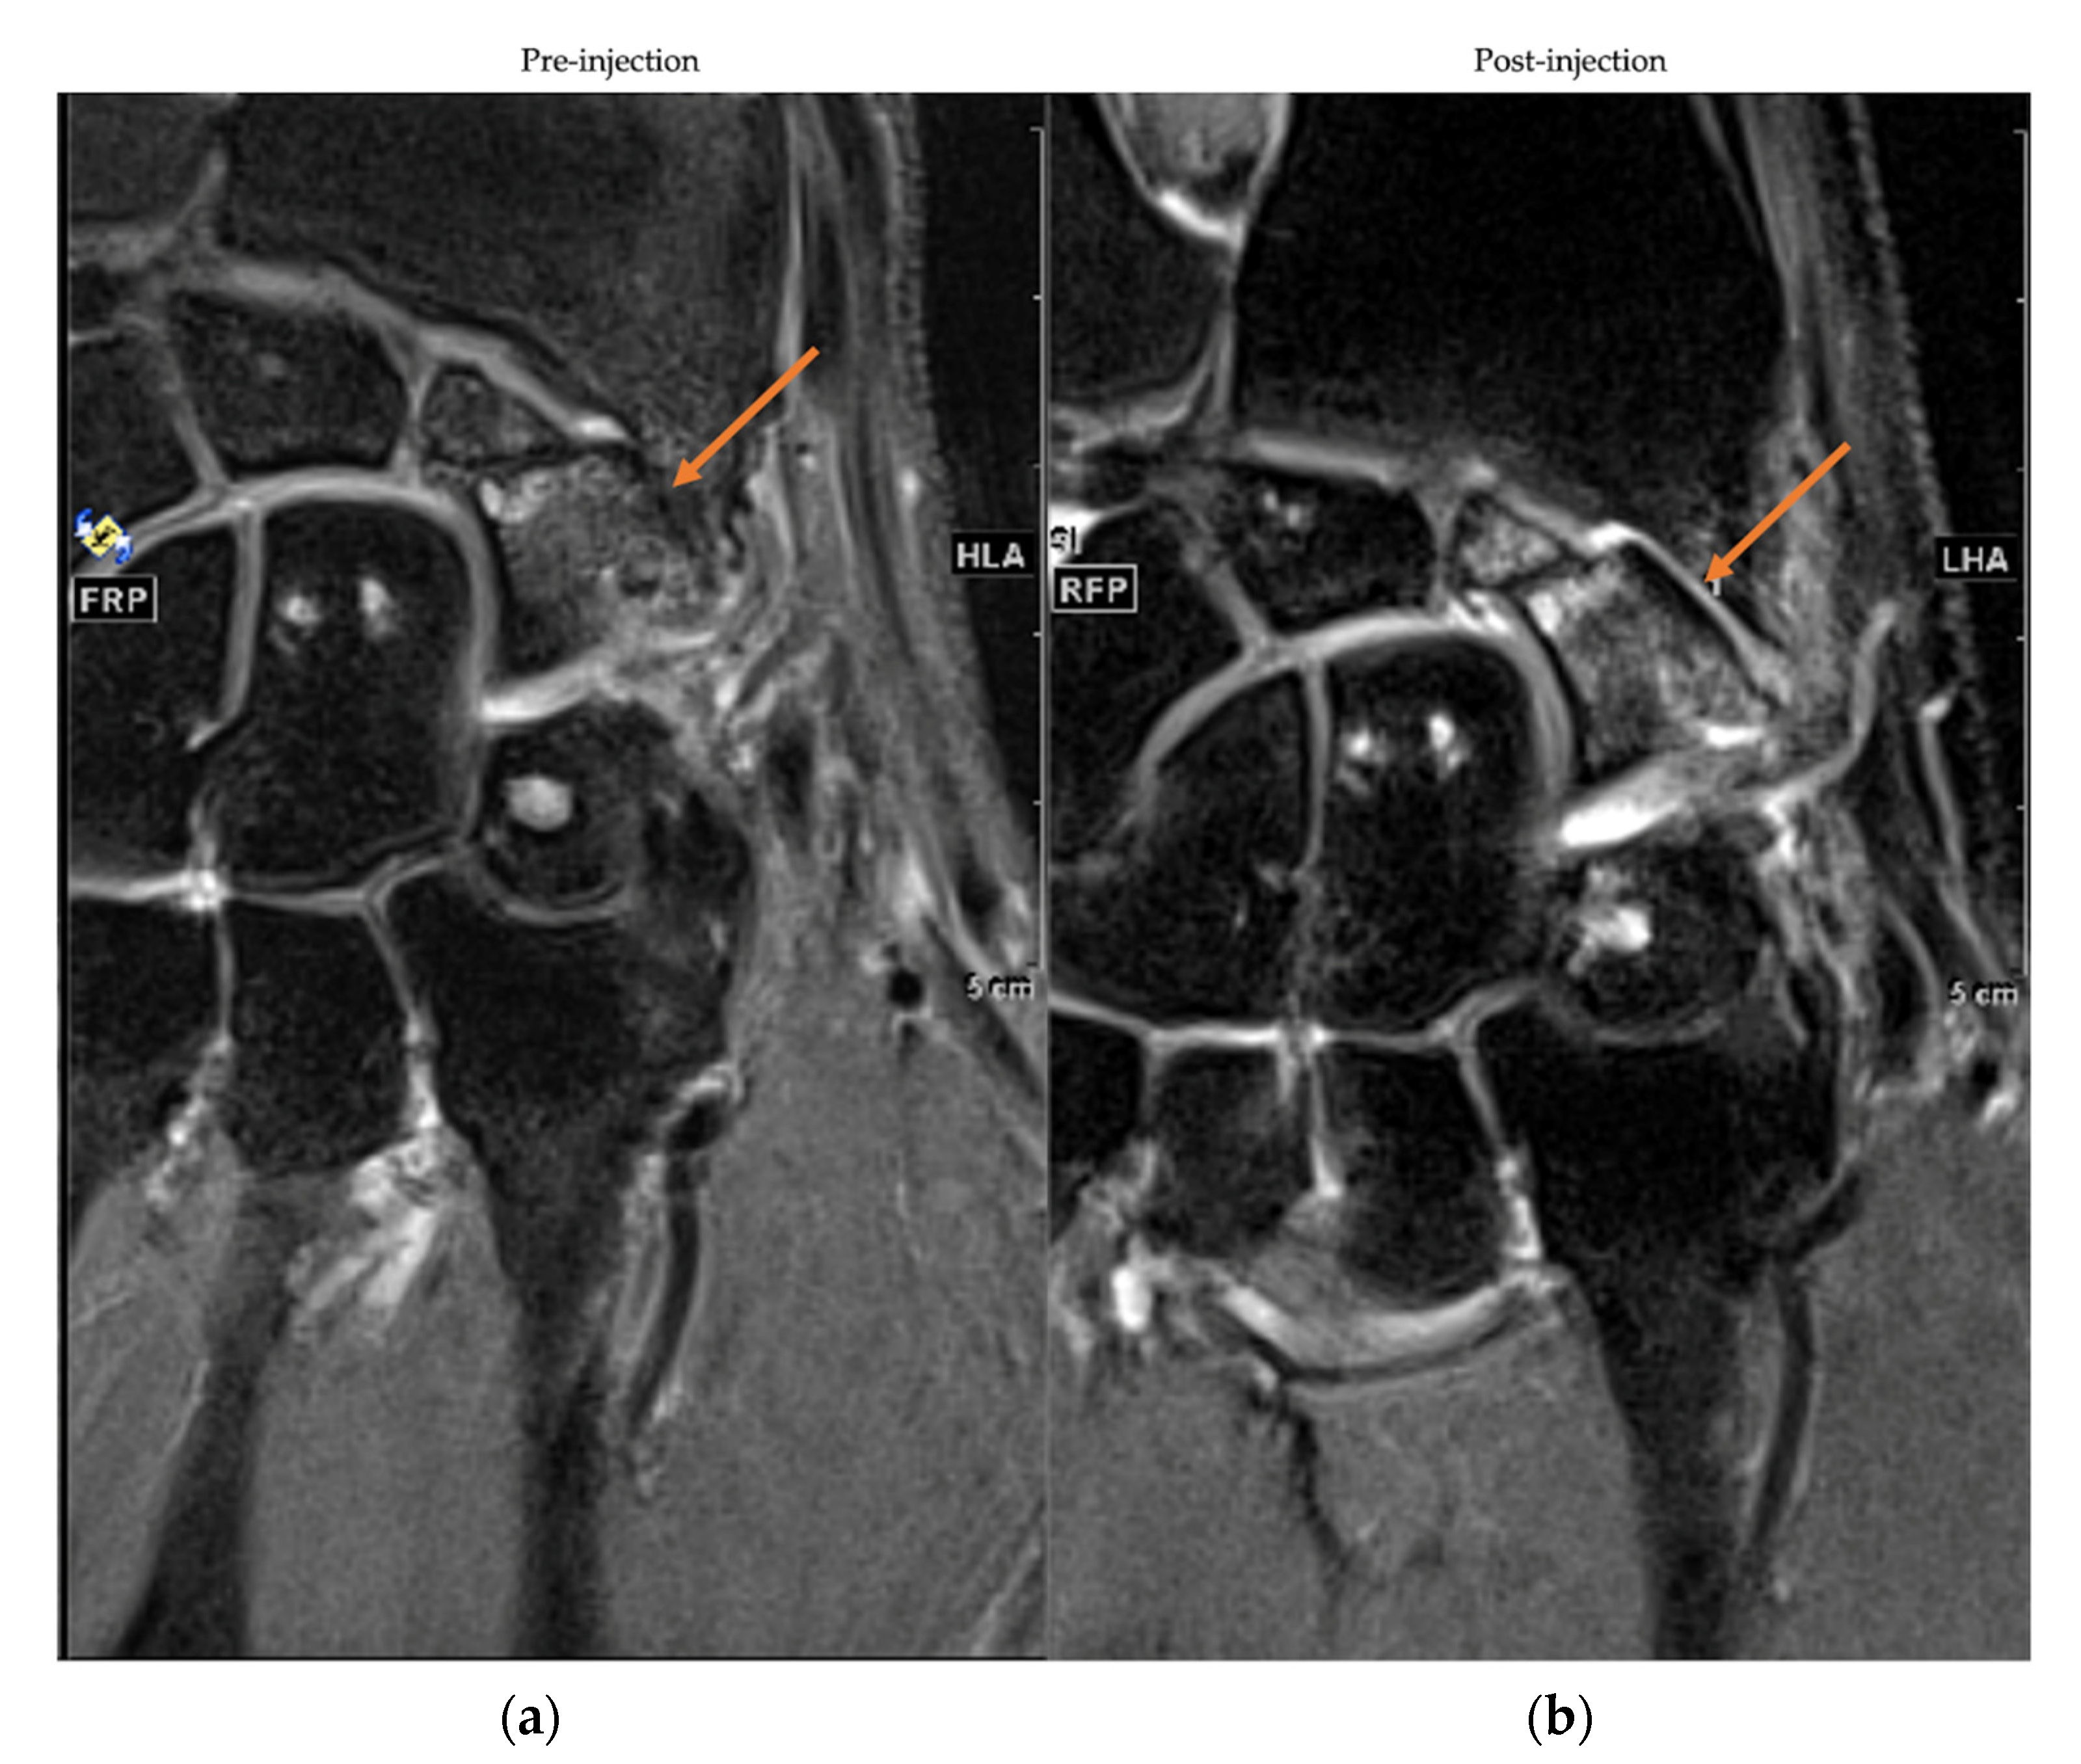

3.5. MRI Assessment